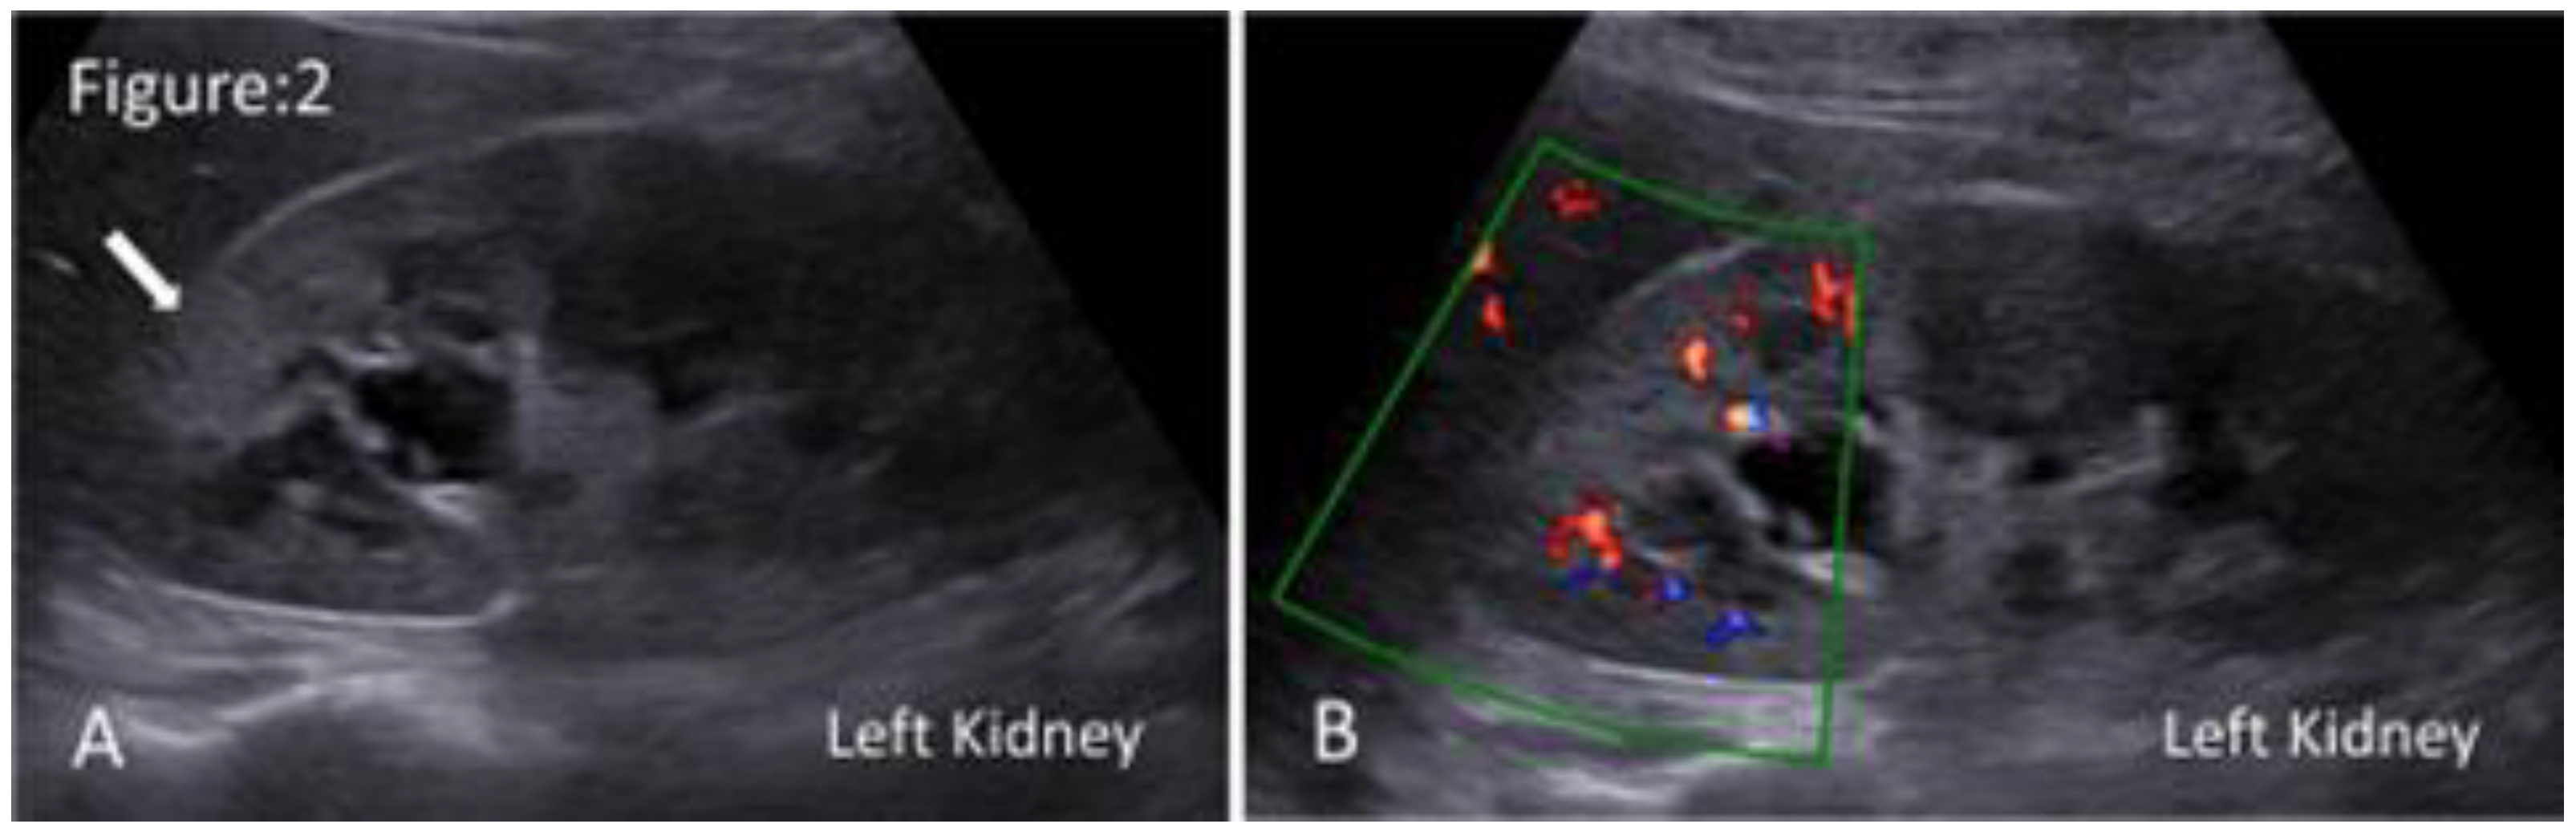

Acute Pyelonephritis

| Ultrasound Feature | Pathological Explanation |

|---|---|

| Generalised enlargement of the kidney (the affected kidney is ≥1.5 cm longer than the unaffected kidney). | Renal parenchymal inflammation results in parenchymal oedema and congestion. |

| Hypoechoic renal parenchyma. | |

| Loss of renal sinus fat. | |

| Loss of corticomedullary differentiation. | |

| Hyperechoic renal parenchyma. | Focal area of parenchymal haemorrhage. |

| Mild hydronephrosis and proximal hydroureter without obvious obstructive cause. | Inhibition of ureteric peristaltic motion, caused by bacterial endotoxins, leads to the dilatation of the pelvicalyceal system. |

| Hyperechoic debris within the dilated pelvicalyceal system. | Renal parenchymal inflammation results in the accumulation of dead neutrophils, bacteria, cellular debris, and proteinaceous material within the dilated pelvicalyceal system. |

| Power Duplex evidence of increased blood flow within the renal vascular system (Flaring kidney). | Renal parenchymal inflammation leads to dilation of the renal vasculature and increased blood flow. |

| Limited renal movements during respiration compared with unaffected kidney. | Inflammatory process and associated oedema result in increased stiffness and decreased compliance of the kidney. |